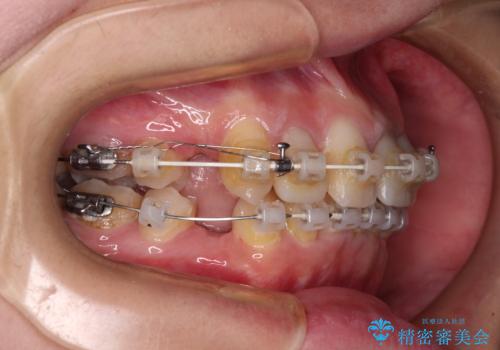

- 矯正装置

- 審美装置

- 前歯のデコボコと、その結果むし歯が進行していることを気にして来院された患者様です。

前歯や奥歯の根管治療を行い、その後上下左右の第一小臼歯4本を抜歯してワイヤー装置にて矯正治療を行うこととしました。